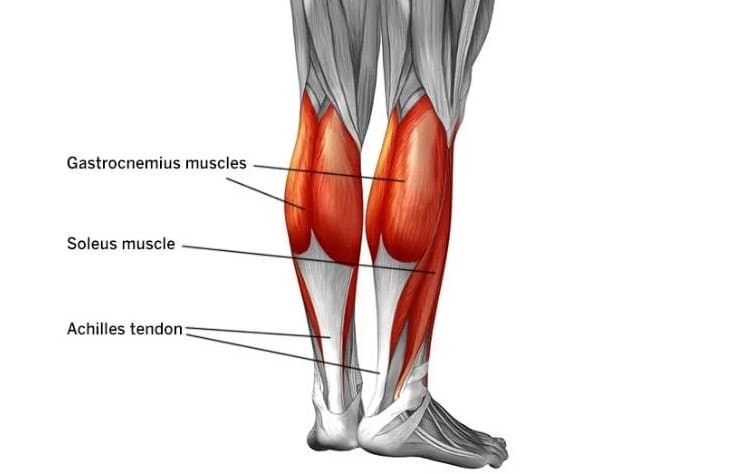

¿Qué son los gemelos y el sóleo? (Tus músculos de la pantorrilla)

Imagina que en la parte de atrás de tu pierna, justo debajo de la rodilla, viven dos músculos fuertes que trabajan juntos. A esos dos se les llama gemelos (porque son como dos hermanos gemelos, son iguales y van a la par). Son los músculos grandes que notas en la pantorrilla. ¿Para qué sirven? Estos “hermanos” poderosos te ayudan a ponerte de puntillas, a saltar y a empujar el pie cuando caminas o corres.

Debajo de estos dos músculos hay otro más profundo llamado sóleo. El sóleo es como un ayudante silencioso: también ayuda a mover el pie, sobre todo cuando tienes la rodilla doblada (por ejemplo, al agacharte). Los gemelos (que están arriba) y el sóleo (que está debajo) forman un equipo de tres músculos muy fuerte en tu pantorrilla. A veces, a este equipo se le llama tríceps sural, pero no te asustes con el nombre. En resumen: gemelos + sóleo = los músculos de tu pantorrilla, los encargados de mover tu pie hacia abajo.

Este equipo de músculos se une a tu hueso del talón mediante un tendón grueso y resistente llamado tendón de Aquiles. Piensa en el tendón de Aquiles como una cuerda fuerte que conecta tus músculos de la pantorrilla con tu talón. Cuando los gemelos y el sóleo se contraen (se aprietan), tiran de esa cuerda y hacen que tu talón se levante. Así es como puedes ponerte de puntillas o empujar el suelo al caminar. ¡Es un sistema fantástico! Pero, ¿qué pasa si la “cuerda” está demasiado tensa? Aquí viene el problema…